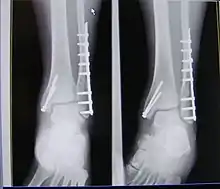

X-ray of trimalleolar fracture repair before and after ORIF surgery

X-ray of trimalleolar fracture repair with plate and nails

Surgical repair using open reduction and internal fixation is generally required, and because there is no lateral restraint of the foot, the ankle cannot bear any weight while the bone knits. This typically takes six weeks in an otherwise healthy person, but can take as much as twelve weeks. Non-surgical treatment may sometimes be considered in cases where the patient has significant health problems or where the risk of surgery may be too great.[1]